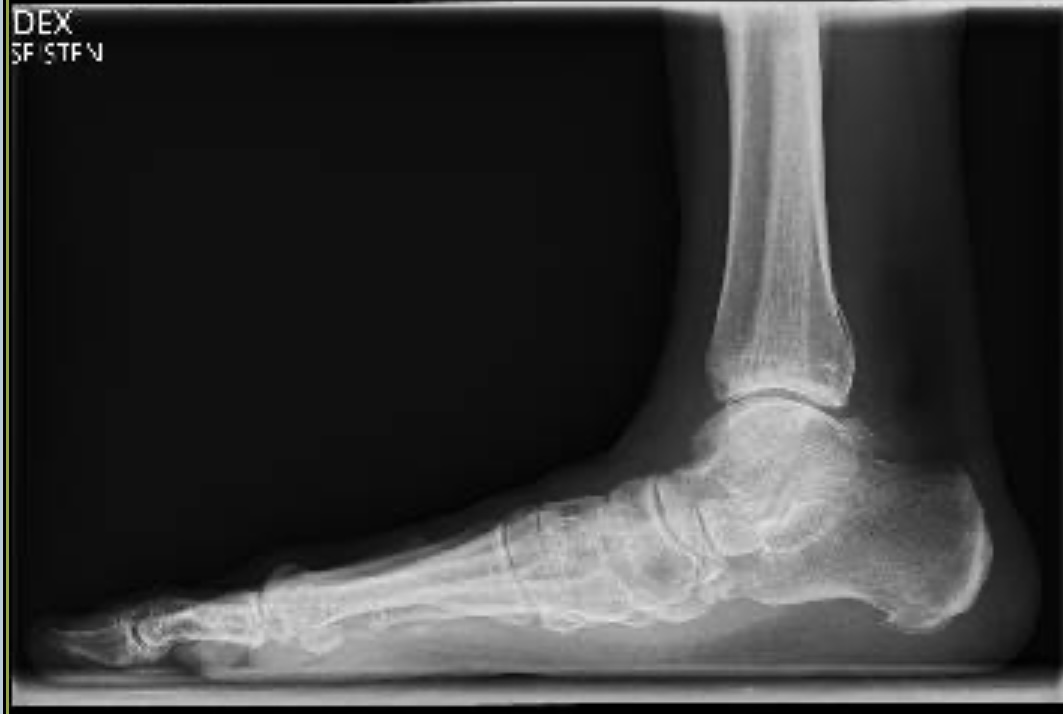

Kuudennen viikon aluksi otettiin uudet röntgen-kuvat – viikon verran etuajassa, koska ortopedi halusi tutkia jatkuneen kipuilun syytä. Oli hiukan pelottavaa hypätä terveellä jalalla kuvaustasanteelle siten, että leikattu jalka oli ilman suojaa, paljaana. Tähän asti jalka oli koko ajan ollut kipsissä tai Walker-saappaassa. Ilman tukea hyppääminen vaati rohkeutta tällaiselta 63-vuotiaalta mummolta. Kuvien mukaan leikkaus oli onnistunut